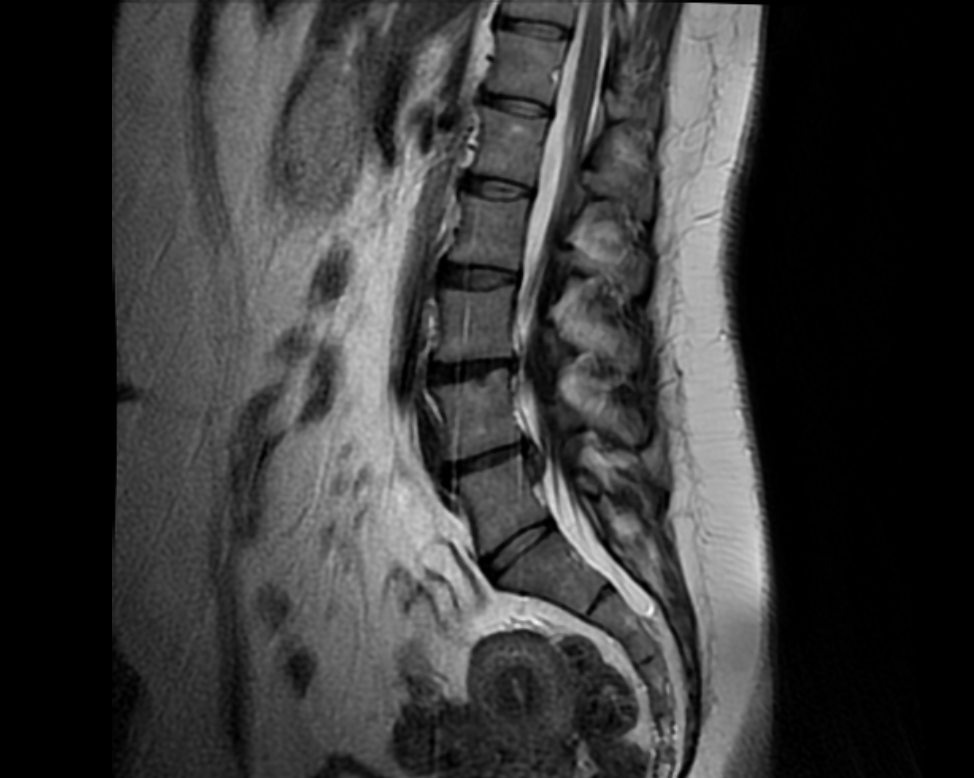

SURGERY ANALYSIS

Computational simulations allow the evaluation of the expected post-surgical behaviour of the analyzed region.

lumbosacral mallado